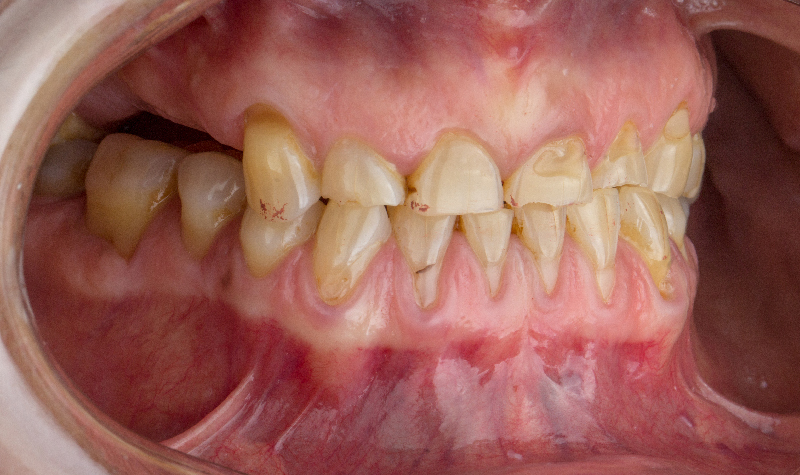

Rehabilitación oral total con prótesis inferior sobre implantes y coronas superiores.

Prótesis híbrida inferior de cerámica fija sobre implantes.